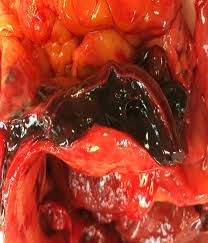

Volume 5 presents the aspects of microcirculation using laser Doppler flow spectrometry from physical, physiological and pathophysiological points of view for clinical use. With the focus on sepsis and SIRS, the measurement of microcirculation is at the center of diagnostic efforts and therapeutic approaches.